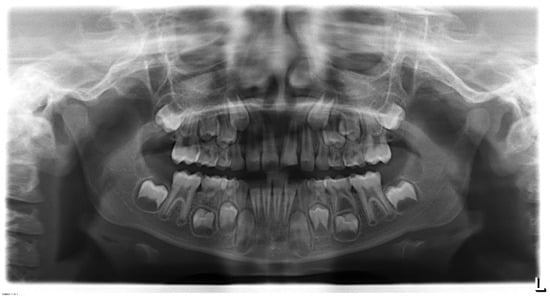

An eight-year-old male patient presented to the pediatric department at Egas Moniz Dental Clinic, Almada Portugal for an emergency appointment 30 days after orofacial trauma. The patient had no significant medical history to report. In clinical evaluation, extraoral examination showed no facial asymmetry or swelling. Intraoral examination showed an uncomplicated crown fracture (enamel and dentin) of the upper left central incisor (21) without fistula, and soft tissue laceration or alveolar bone fracture (Figure 1). In the diagnostic test, the tooth did not show any response to the different pulp test. The radiographic examination revealed incomplete root development and absence of periapical lesion (Figure 2). Taking clinical and radiographic findings into account, the concluded diagnosis was pulp necrosis.

Figure 1.

Intra-oral frontal photography. (A) Preoperative buccal clinical view of the anterior teeth. (B) Preoperative incisal clinical view of the anterior teeth.